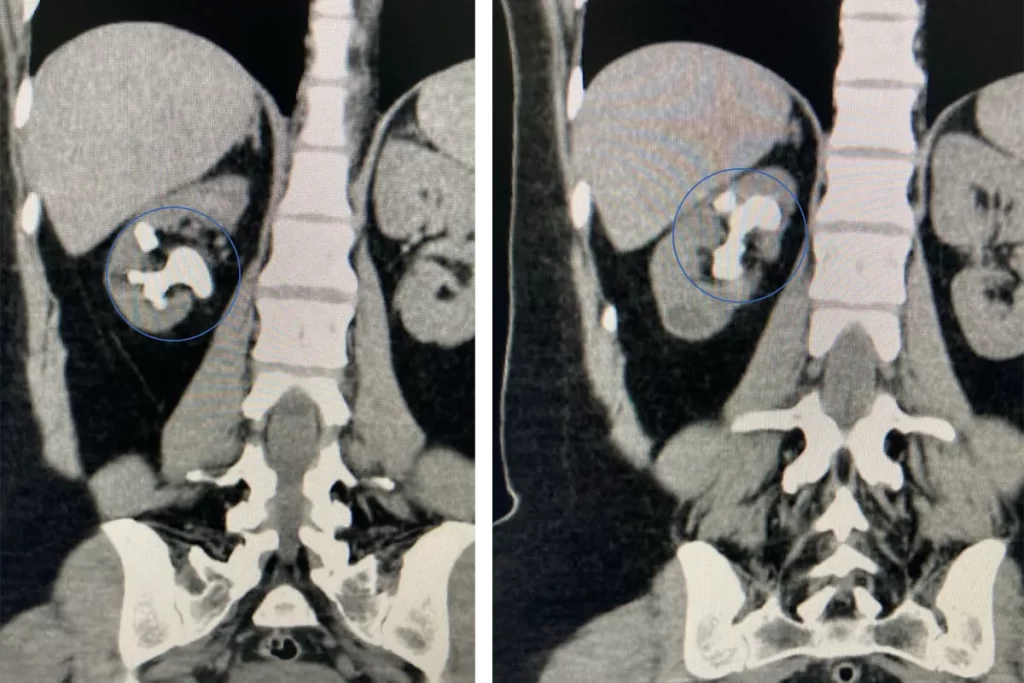

Na tomografia computadorizada, os cálculos aparecem claramente com tamanho significativo, inviabilizando métodos não invasivos. Essa condição exige tratamento rápido para preservar a função renal e aliviar as dores intensas.